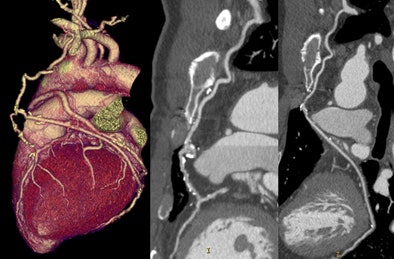

| A 47-year-old man with new chest pain five years after coronary artery bypass grafting (CABG). CTA effective dose using PGA technique was 3.87 mSv. Volume-rendered view of the heart depicts a complex bifurcated left internal mammary artery (LIMA) graft. The LIMA is anastomosed to the left anterior descending (LAD) coronary artery (center) and a radial artery branch connects the mid-LIMA to the second obtuse marginal branch (right). Both grafts and runoff arteries are widely patent. |